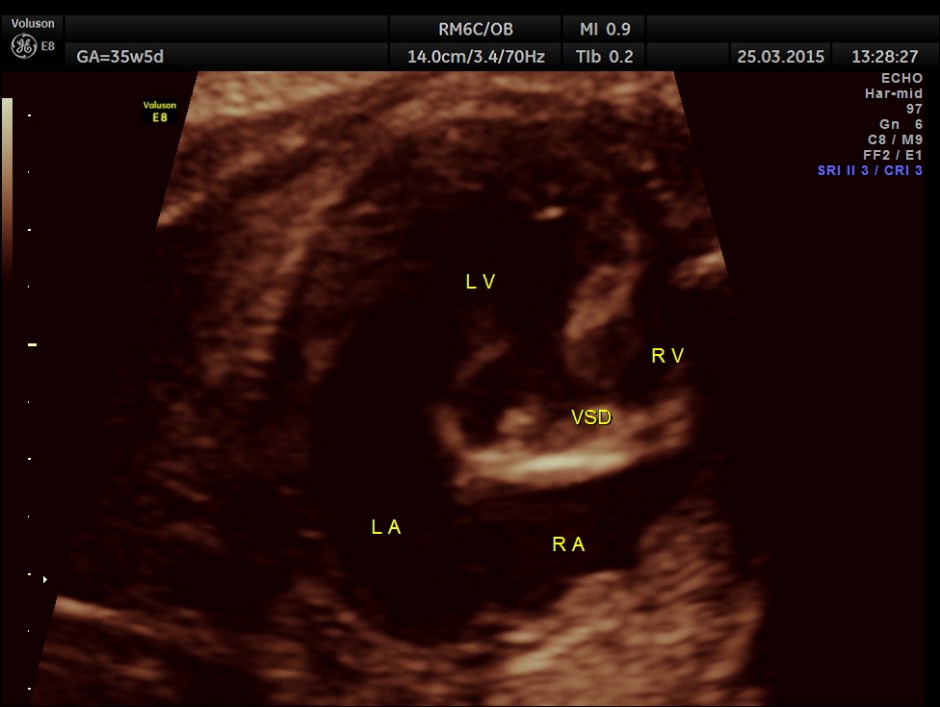

Ventricular Septal Defect is seen.

Ventricular Septal Defect is seen .

The 4 chamber view showed LV to be dilated.